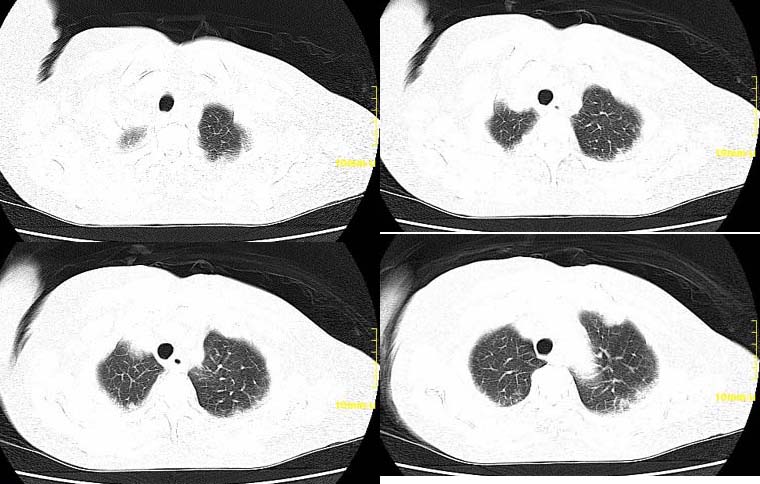

请大家讨论右下肺占位性质。ct值约35-55hu

右肺门后侧软组织肿块,内见点状钙化,年龄76,ct值约35-55hu ,考虑肺癌可能

右下肺癌右肺门淋巴结转移,双肺转移?建议hrct检查。

右下中央型肺癌伴右肺门淋巴结转移、右肺转移。

右肺门后侧环绕支气管的软组织肿块,内见点状钙化,远端有阻塞性炎症,年龄76,ct值约35-55hu ,考虑右肺中心型肺癌。建议支气管镜鉴。

右下中央型肺癌伴右肺门、纵隔淋巴结转移,双肺肺转移

右下肺中央型肺癌伴阻塞性炎症,并右肺门淋巴结及右肺转移